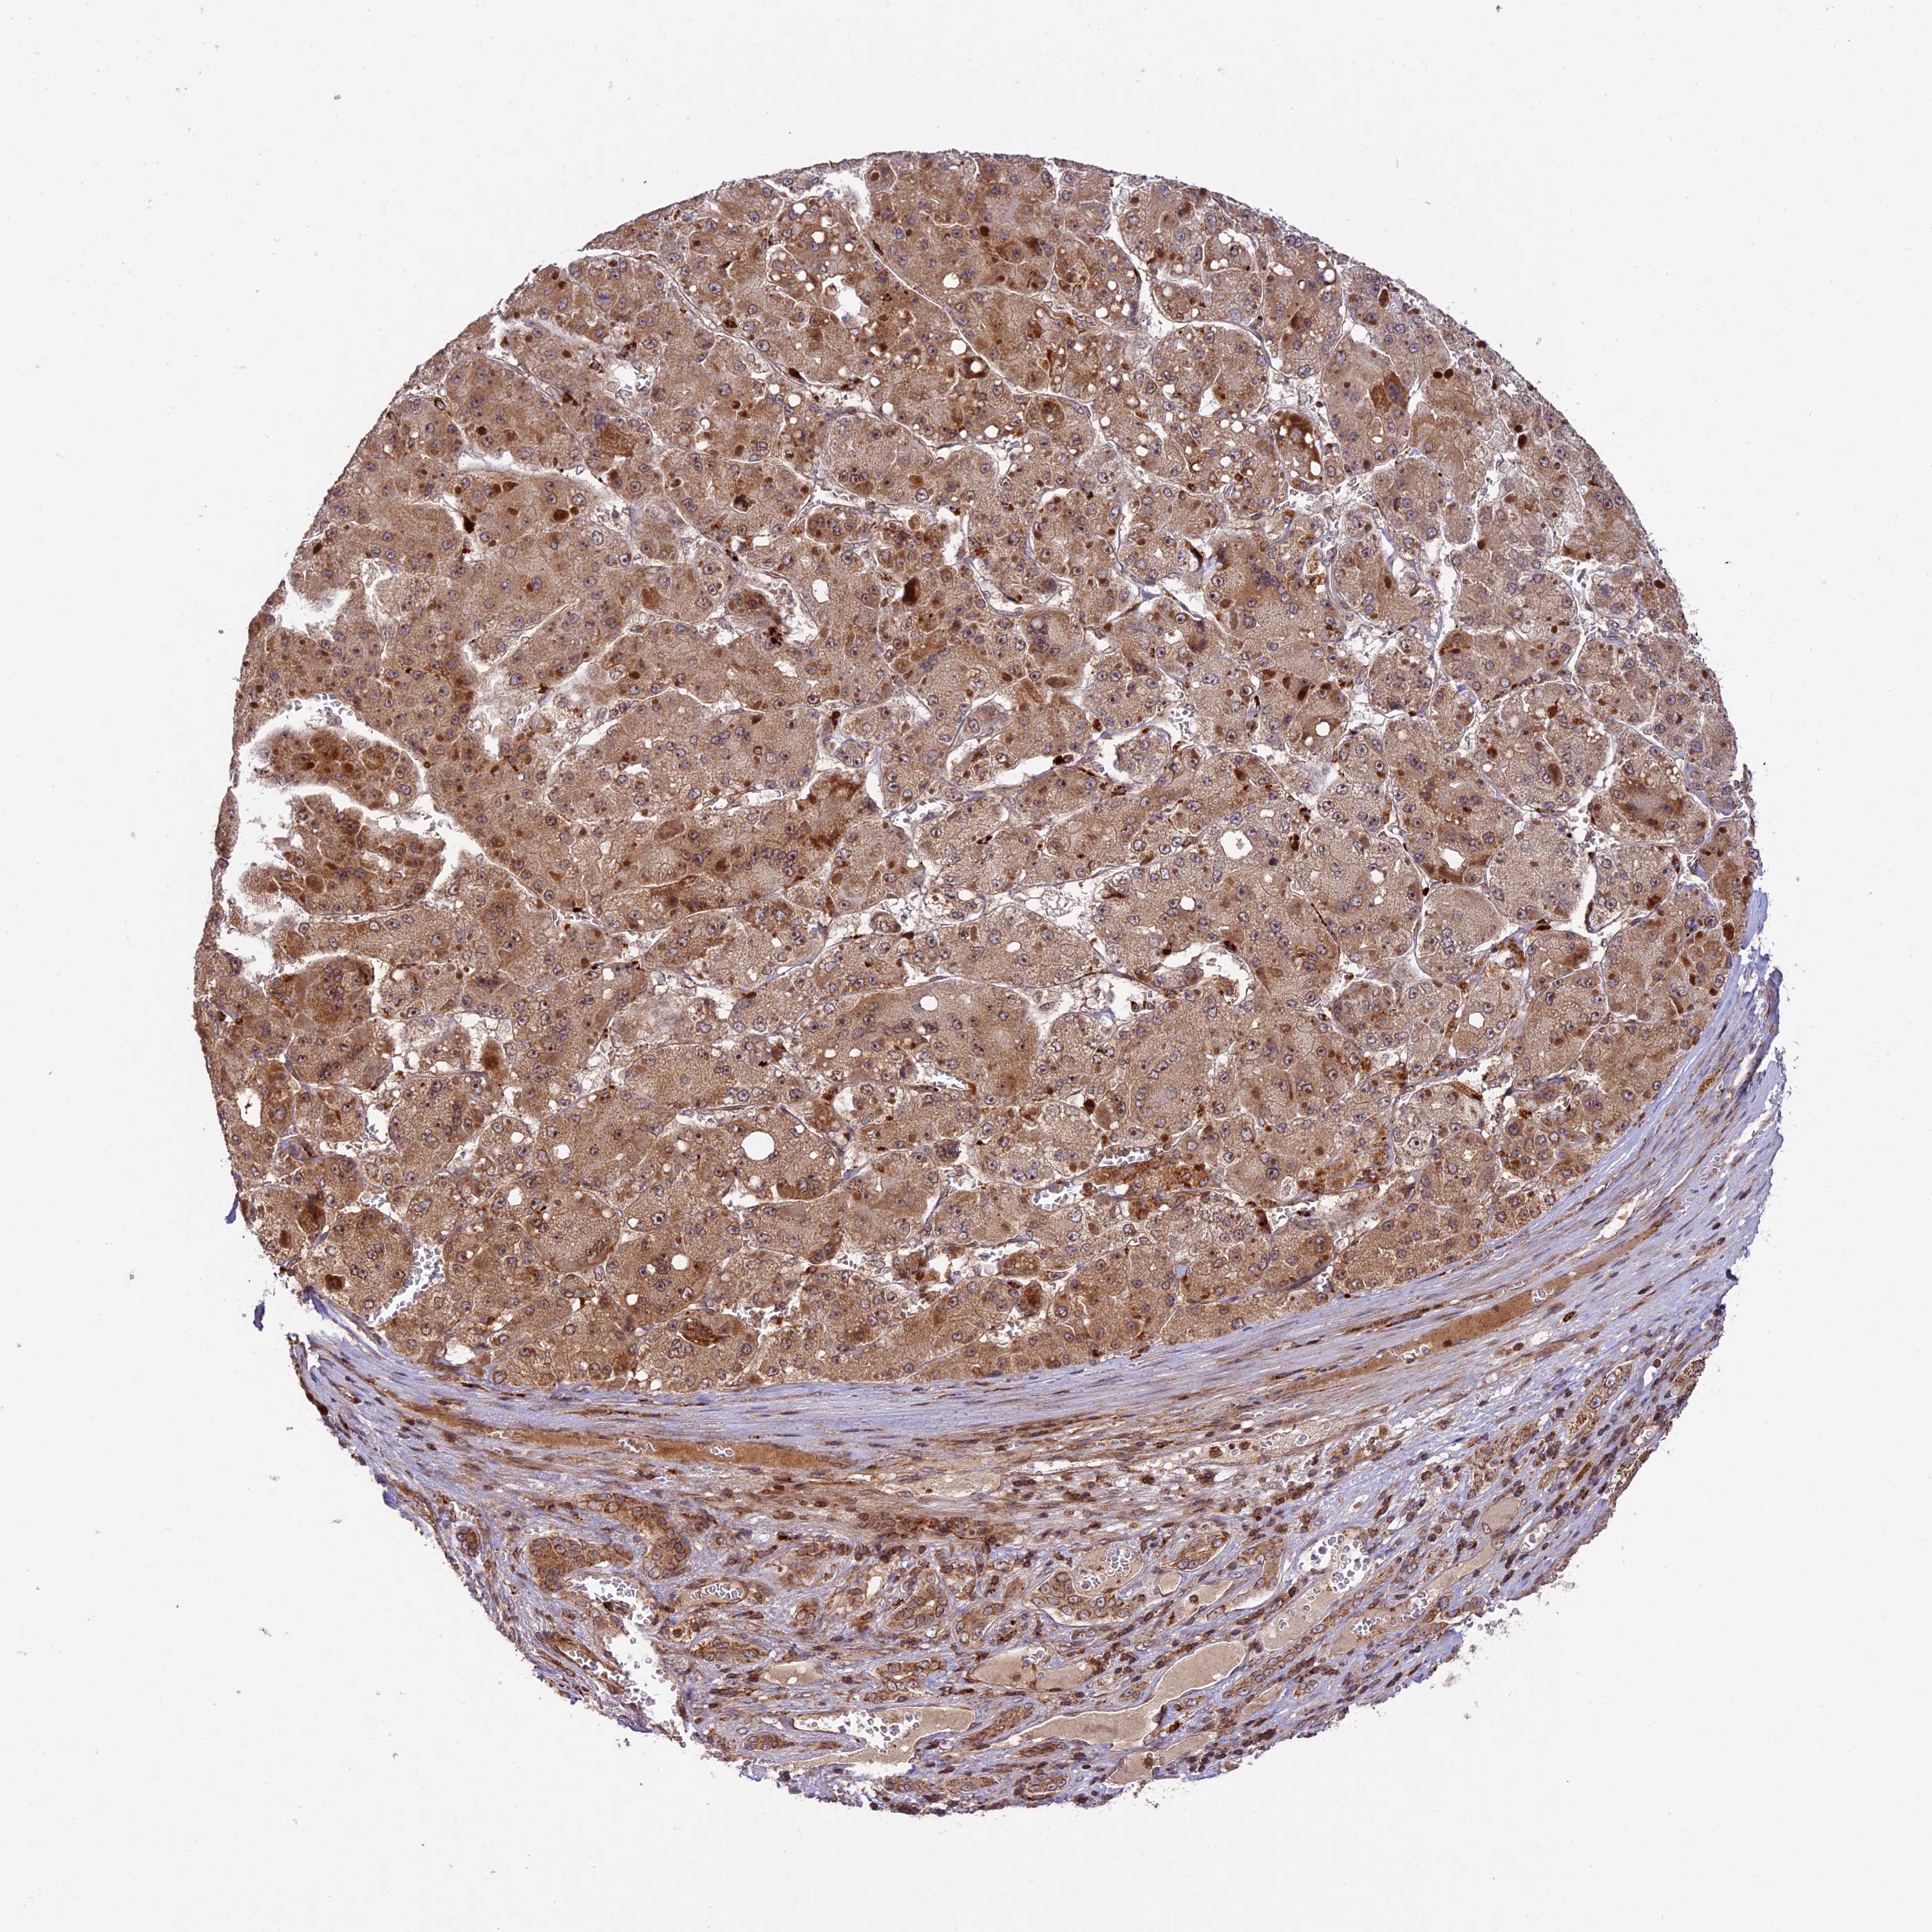

LIVER CANCER - Protein expressioni

A mouse-over function shows sample information and annotation data. Click on an image to view it in a full screen mode. Samples can be filtered based on level of antibody staining by selecting one or several of the following categories: high, medium, low and not detected. The assay and annotation is described here.

Note that samples used for immunohistochemistry by the Human Protein Atlas do not correspond to samples in the TCGA dataset.

Antibody stainingi

Antibody staining in the annotated cell types in the current human tissue is reported as not detected, low, medium, or high, based on conventional immunohistochemistry profiling in selected tissues. This score is based on the combination of the staining intensity and fraction of stained cells.

Each image is clickable and will lead to virtual microscopy that enables deeper exploration of all samples and also displays staining intensity scores, fraction scores and subcellular localization as well as patient and tissue information for each sample.

Antibody HPA039533

Antibody HPA040355

Staining

High

Medium

Low

Not detected

Intensity

Strong

Moderate

Weak

Negative

Quantity

>75%

75%-25%

<25%

None

Location

Nuclear

Cytoplasmic/membranous

Cytoplasmic/membranous,nuclear

Cholangiocarcinoma

Carcinoma, Hepatocellular, NOS